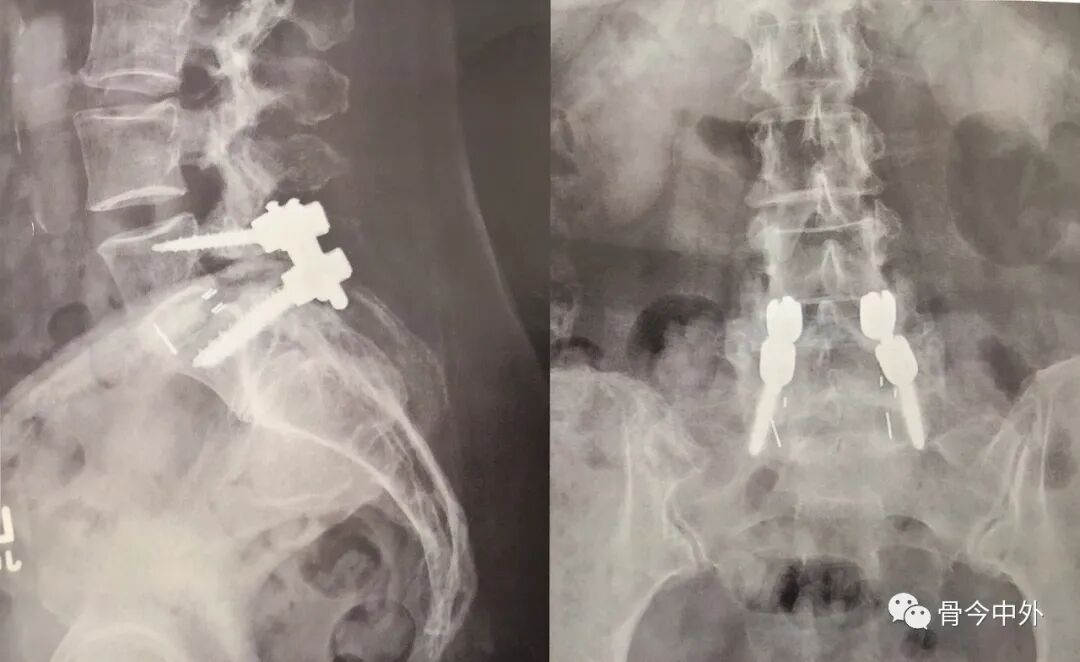

在术后及术后1个月、3个月(图5)和12个月随访时行腰椎X线片检查,显示内固定位置良好,无螺钉退出或松动。术后1个月随访时,腿部麻木和根性疼痛改善。术后12个月,所有症状完全缓解,并通过以前无法参加的锻炼计划减掉了9kg体重。

图5 术后正位(右)和侧位(左)X线片显示L5~S1后路腰椎椎间融合,L5皮质骨螺钉固定。